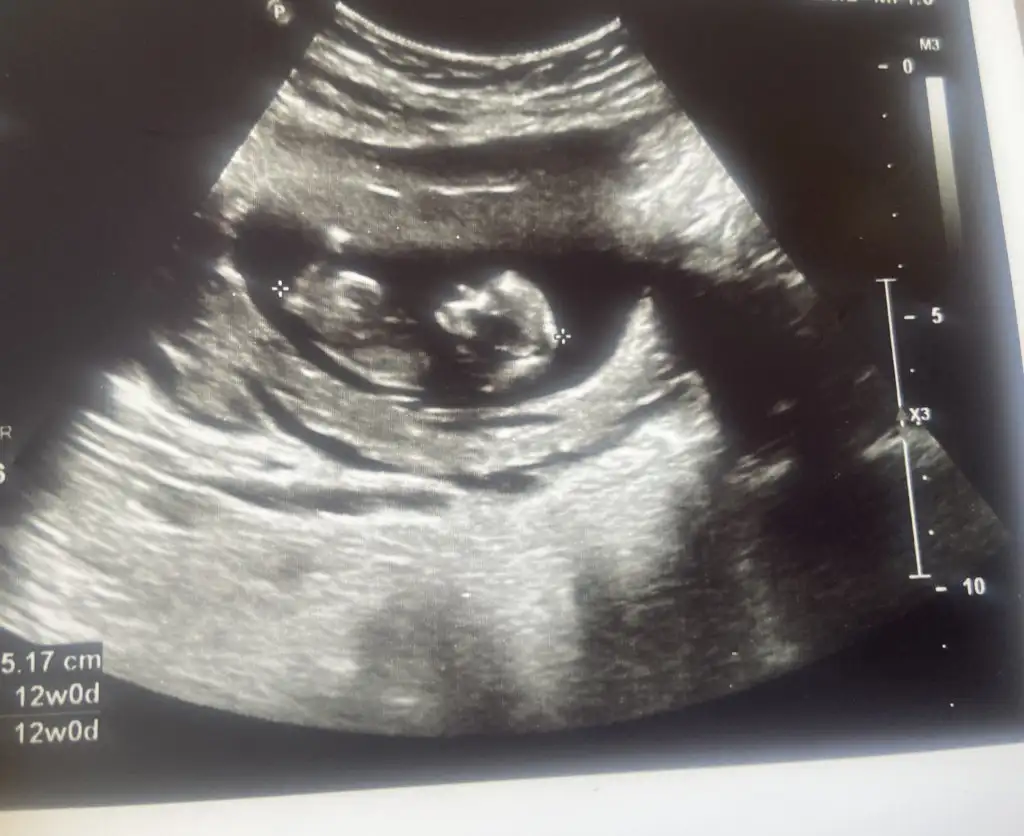

Öncelikle çok geçmiş olsun 🙏🏻 aynı durumu yaşadım ve 3 martta kürtaj oldum. Drum ara vermeye gerek yok dedi, lekelenme biter bitmez deneyebilirsiniz dedi. Ben hemen olacağına inanmıyordum ama kürtaj sonrası ilk adeti oldum 2.adeti göremedim😅 şu an 13+5 iz ve herşey yolunda🙏🏻